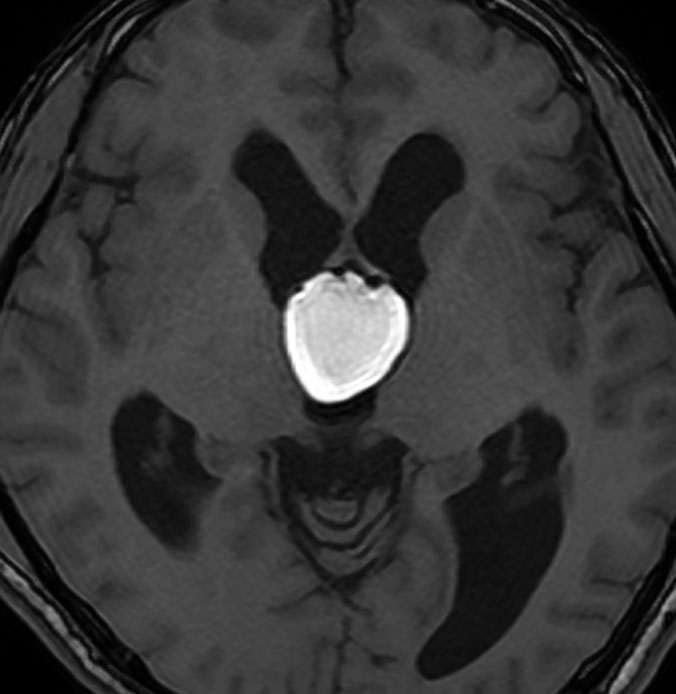

コロイド嚢胞 (colloid cyst)とは,第3脳室に発生するコロイド嚢胞のことです。第3脳室前半部上壁,特にモンロー孔の内側中心部に多く発生するので,脳弓よりは下方で,脈絡組織(tela choroidea)にぶら下がるような位置にあります。第3脳室前半を満たすように増大し,中脳水道方向へと伸展します。発生起原については,内胚葉由来とされ,midline maldevelopmental inclusin defectによる胎生期遺残嚢胞として捉えられます。

MRI診断により偶然発見される無症候性の10 mm以下の小さなものが最も多いです。しかし,緩徐に増大してモンロー孔を閉塞して水頭症をきたすとき症候性となることがあります。急激な症状を呈するものでは嚢胞内出血が見られ,きわめて稀ではあるが急性水頭症にて突然死したという報告あります。

頻度としては30-40代の男性に多く,モンロー孔を閉塞して水頭症をきたし発症します。従って,間欠的な激しい頭痛,あるいは持続痛,嘔気,嘔吐が臨床症状です。項部硬直などの他覚的な神経症候は認められません。稀に頭痛,嘔吐に続発して急激な意識障害を生じることがあります。時には,緩徐進行性の閉塞性水頭症で、歩行障害、視力低下、認知機能低下などを呈することがあります。

第3脳室内にはさまざまな嚢胞性病変が発生しますが,第3脳室内部の発生母地で鑑別ができます。例えば,前上方に類円形の腫瘤を認めたときにはコロイドのう胞をもっとも強く疑い,逆に後方であればのう胞性松果体腫瘍を疑います。一般的にCTでは等吸収から高吸収域を示し,MRIではT1, T2強調画像ともに高信号を呈することが多いといえます。造影剤で嚢胞壁の増強効果を認めることはとても稀です。